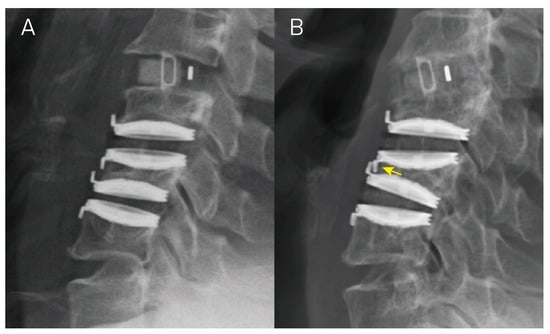

2.2. Radiographic Evaluation